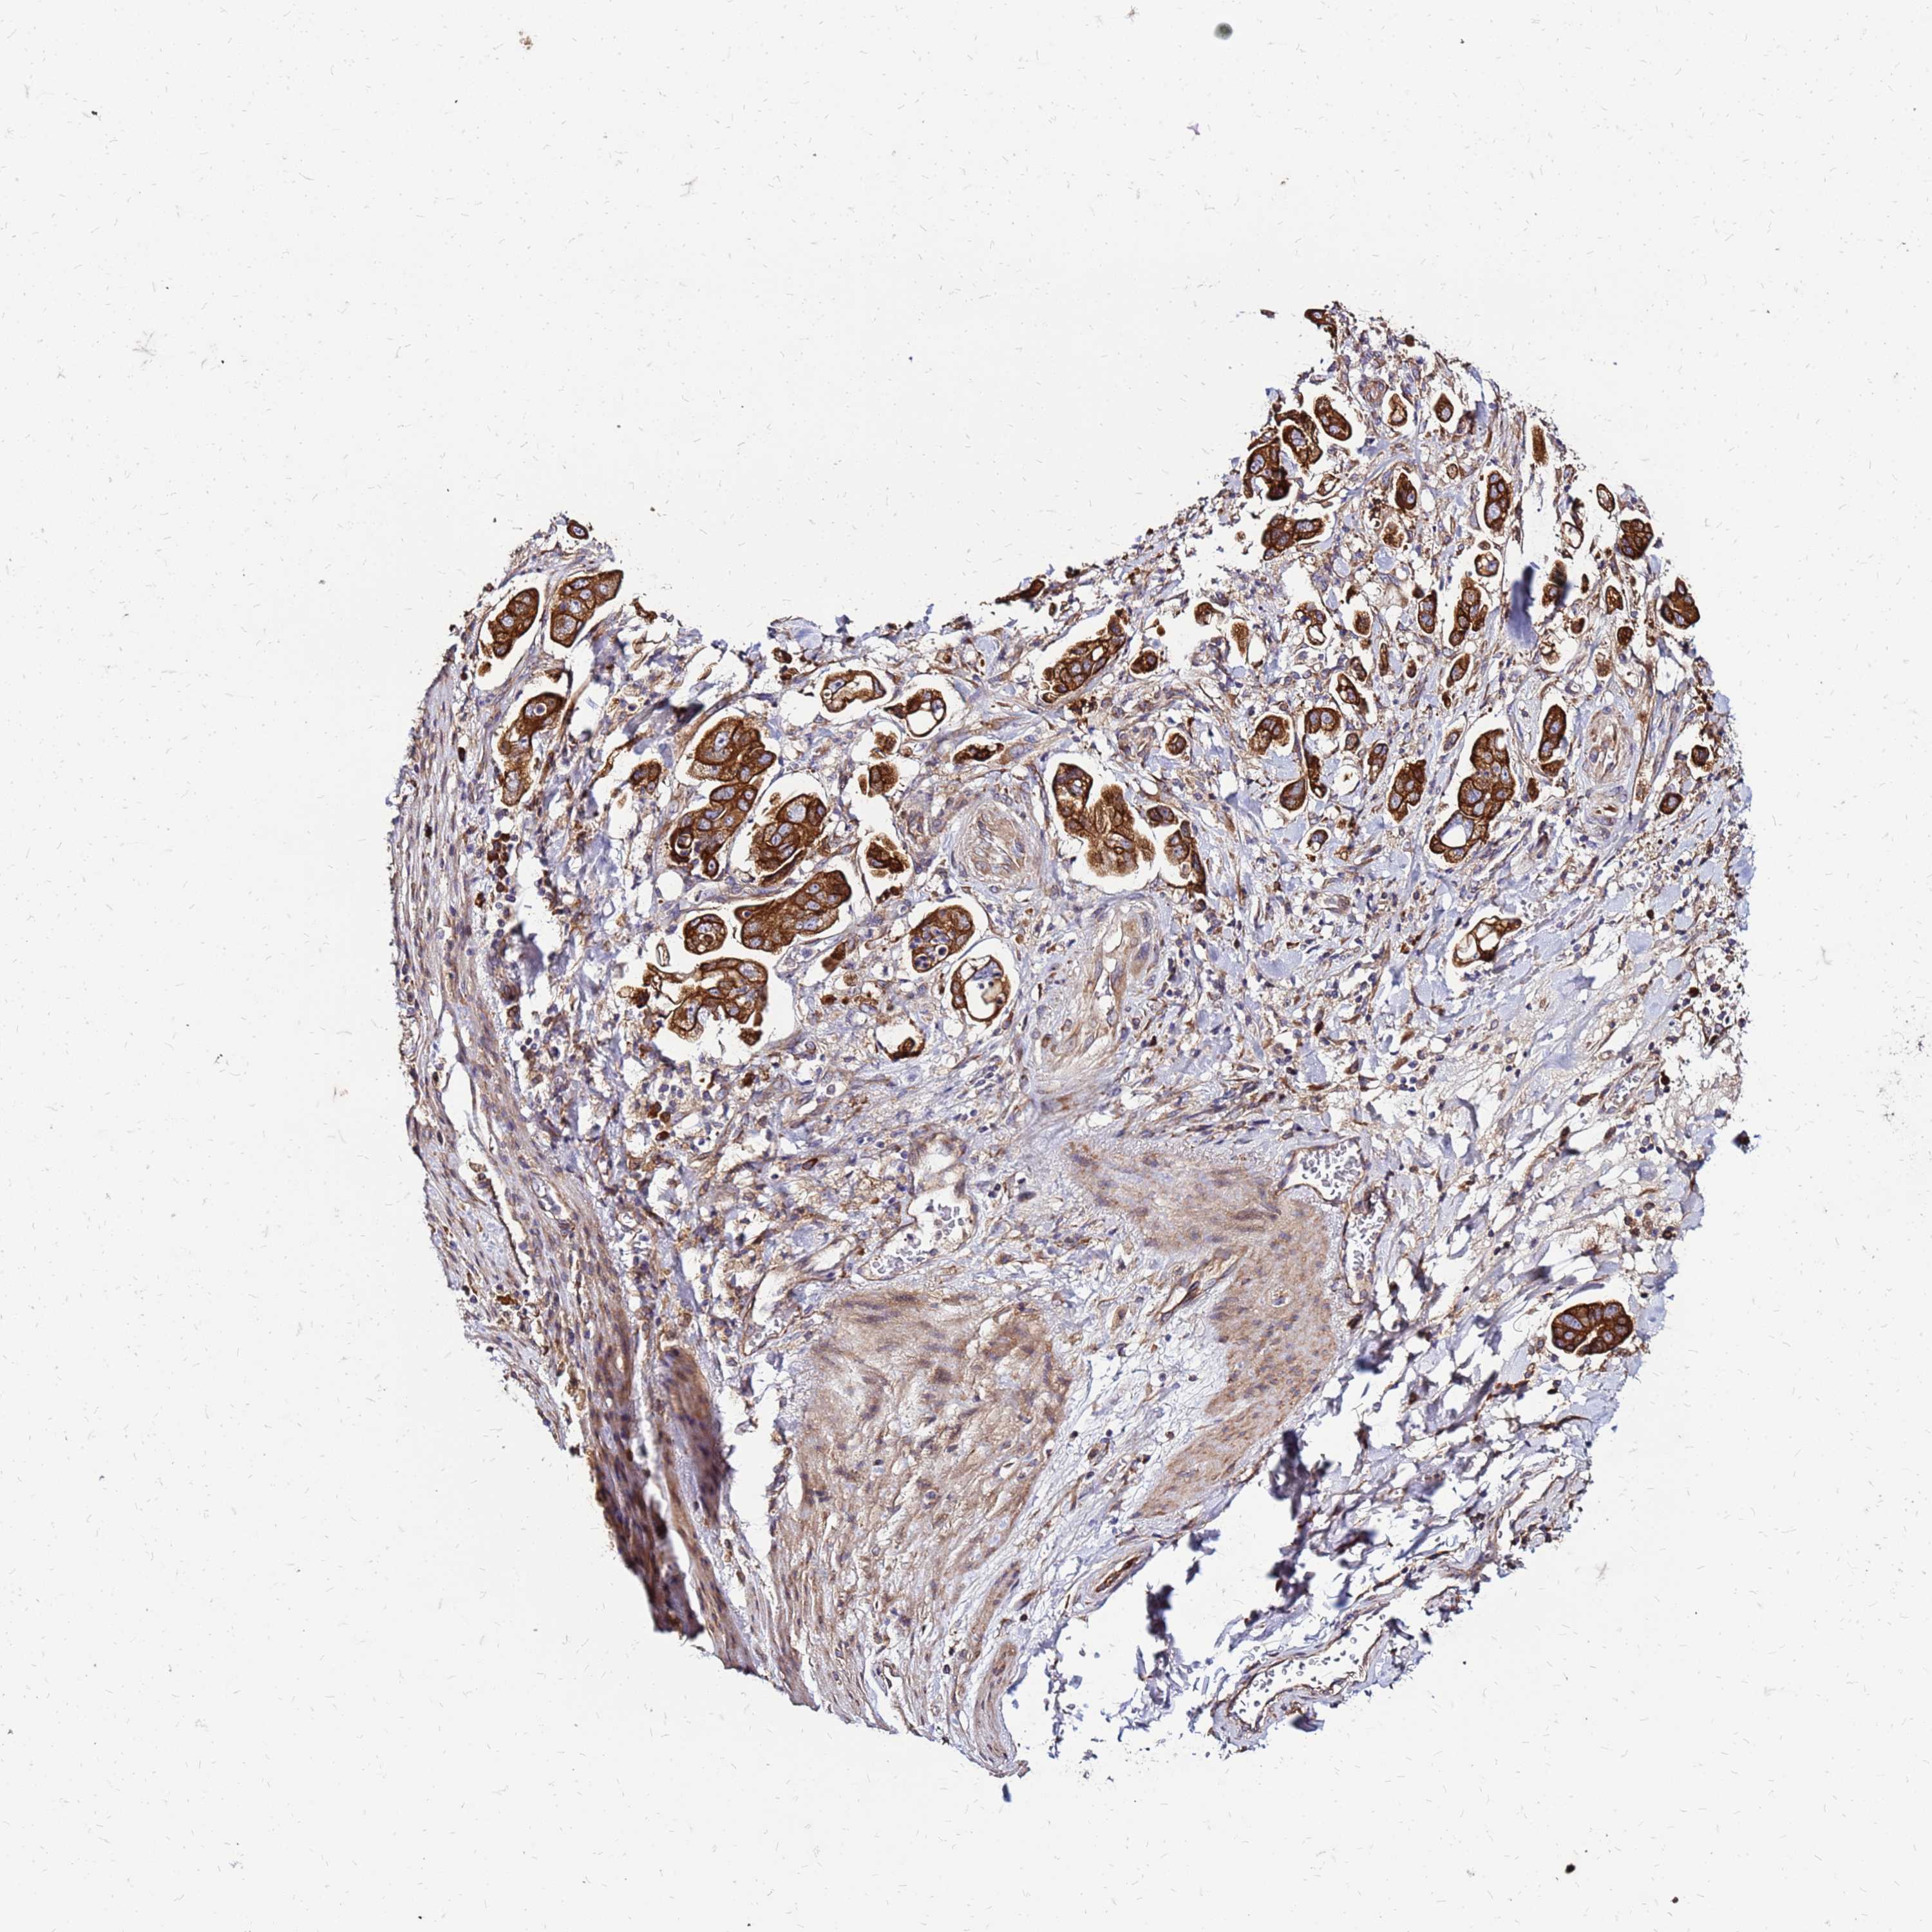

STOMACH CANCER - Protein expressioni

A mouse-over function shows sample information and annotation data. Click on an image to view it in a full screen mode. Samples can be filtered based on level of antibody staining by selecting one or several of the following categories: high, medium, low and not detected. The assay and annotation is described here.

Note that samples used for immunohistochemistry by the Human Protein Atlas do not correspond to samples in the TCGA dataset.

Antibody stainingi

Antibody staining in the annotated cell types in the current human tissue is reported as not detected, low, medium, or high, based on conventional immunohistochemistry profiling in selected tissues. This score is based on the combination of the staining intensity and fraction of stained cells.

Each image is clickable and will lead to virtual microscopy that enables deeper exploration of all samples and also displays staining intensity scores, fraction scores and subcellular localization as well as patient and tissue information for each sample.

Antibody HPA023038

Staining

High

Medium

Low

Not detected

Intensity

Strong

Moderate

Weak

Negative

Quantity

>75%

75%-25%

<25%

None

Location

Nuclear

Cytoplasmic/membranous

Cytoplasmic/membranous,nuclear

Adenocarcinoma, NOS